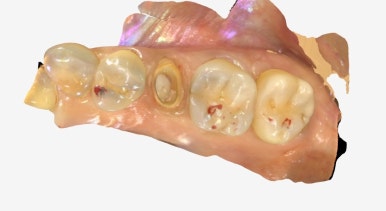

파절된 보철을 제거한 뒤,

치아 상태를 정밀하게 체크했습니다.

✅ 다행히 치아 뿌리와 구조 모두 건강했고,

✅ 신경치료나 추가 보강 없이 바로 재보철이 가능했어요.